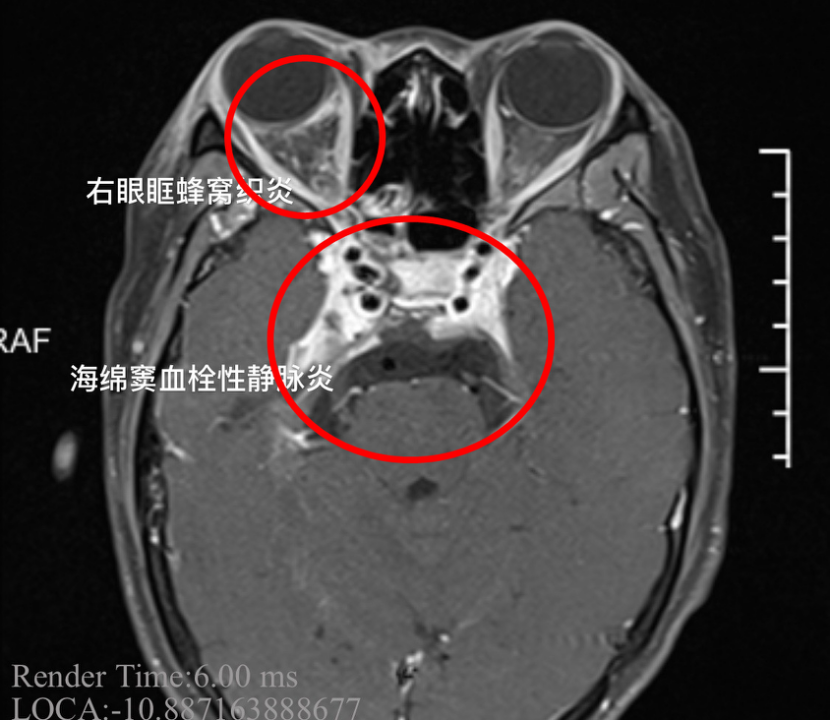

小杨患上了“海绵窦血栓性静脉炎”

这是一种严重的颅内感染

患者刚来的时候,病情是比较严重的,体温持续在39℃以上。女孩的右眼外凸,眼球已经固定无法转动,瞳孔扩大,对光反射消失,多组颅神经受累,这都是海绵窦严重感染的征象。同时我们发现患者的脑膜刺激征阳性,海绵窦的炎症已经扩散,出现了脑膜炎,继续进展随时有生命危险。